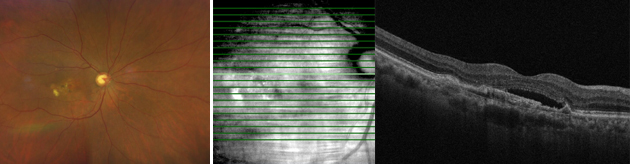

망막하출혈, 망막하액이 흡수된 황반변성

치료 후